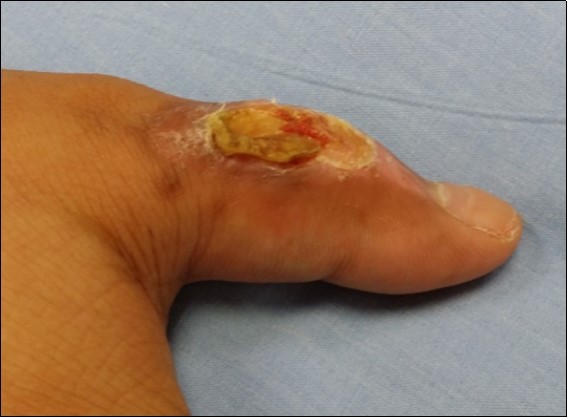

Case no 3. 42 y/o, male. Crush injury with soft tissue defect of volar side of the left thumb. (Figure 9, Figure 10, Figure 11, Figure 12, Figure 13.)

Figure 9.4 days post-op

4 days post-op